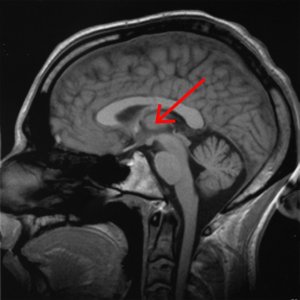

A brain scan illustrating the location of the thalamus in the

human brain. Source: Wikipedia

The thalamus is a structure deep inside the brain that acts like the central control unit of the brain. Everything coming into the brain from the spinal cord, passes through the thalamus. And everything leaving the brain, passes through the thalamus. It is aware of most everything that is going on and it plays an important role in the regulation of movement. Importantly it is biased towards inhibiting movement – a signal from the basal ganglia has to be pretty strong, for the thalamus to give the green light and a particular movement can then be made.